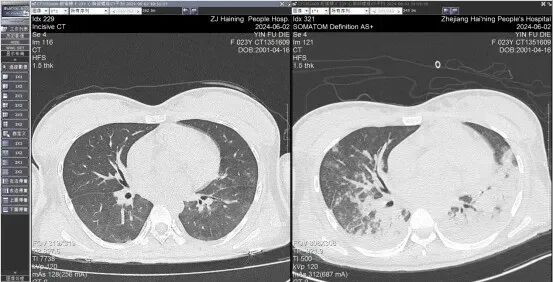

血红蛋白及血小板指标急剧下降,呼吸愈来愈急促,复查肺部CT发现,小殷的肺几乎在24小时内“白”了一半,心率也突然在一夜之间从原来的100次左右下降到最慢45次,心功能的指标也急剧变差。